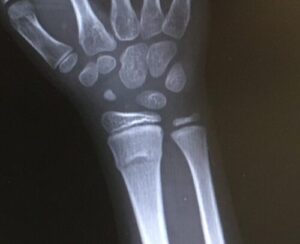

サッカー教室でゲームをしているときに子供が転んで手を痛めました。

痛みの場所が手首からずれていたのと、痛みも強かったので、すぐに病院に連れて行きました。

すると、案の定、骨折。

去年秋に指を骨折し、今年1月には左腕を骨折し救急車で運ばれ、手術をするかしないかの大けが。

先月ようやく最後の通院が終わったと思っていたら、今度は右手首。